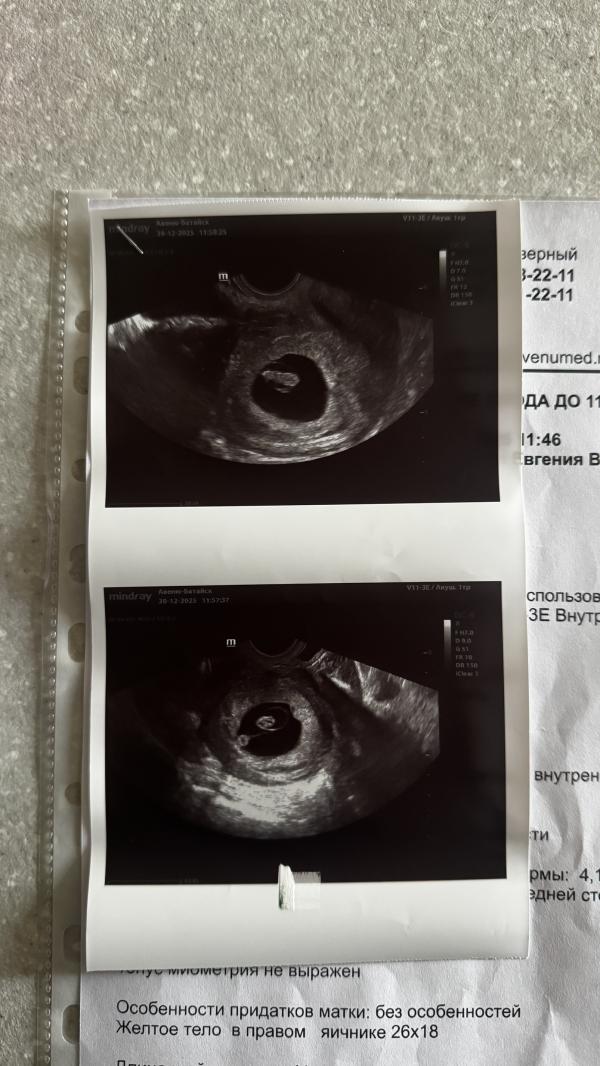

Единственный, по размерам срок 7,6 , а по месячным 7,2 😁